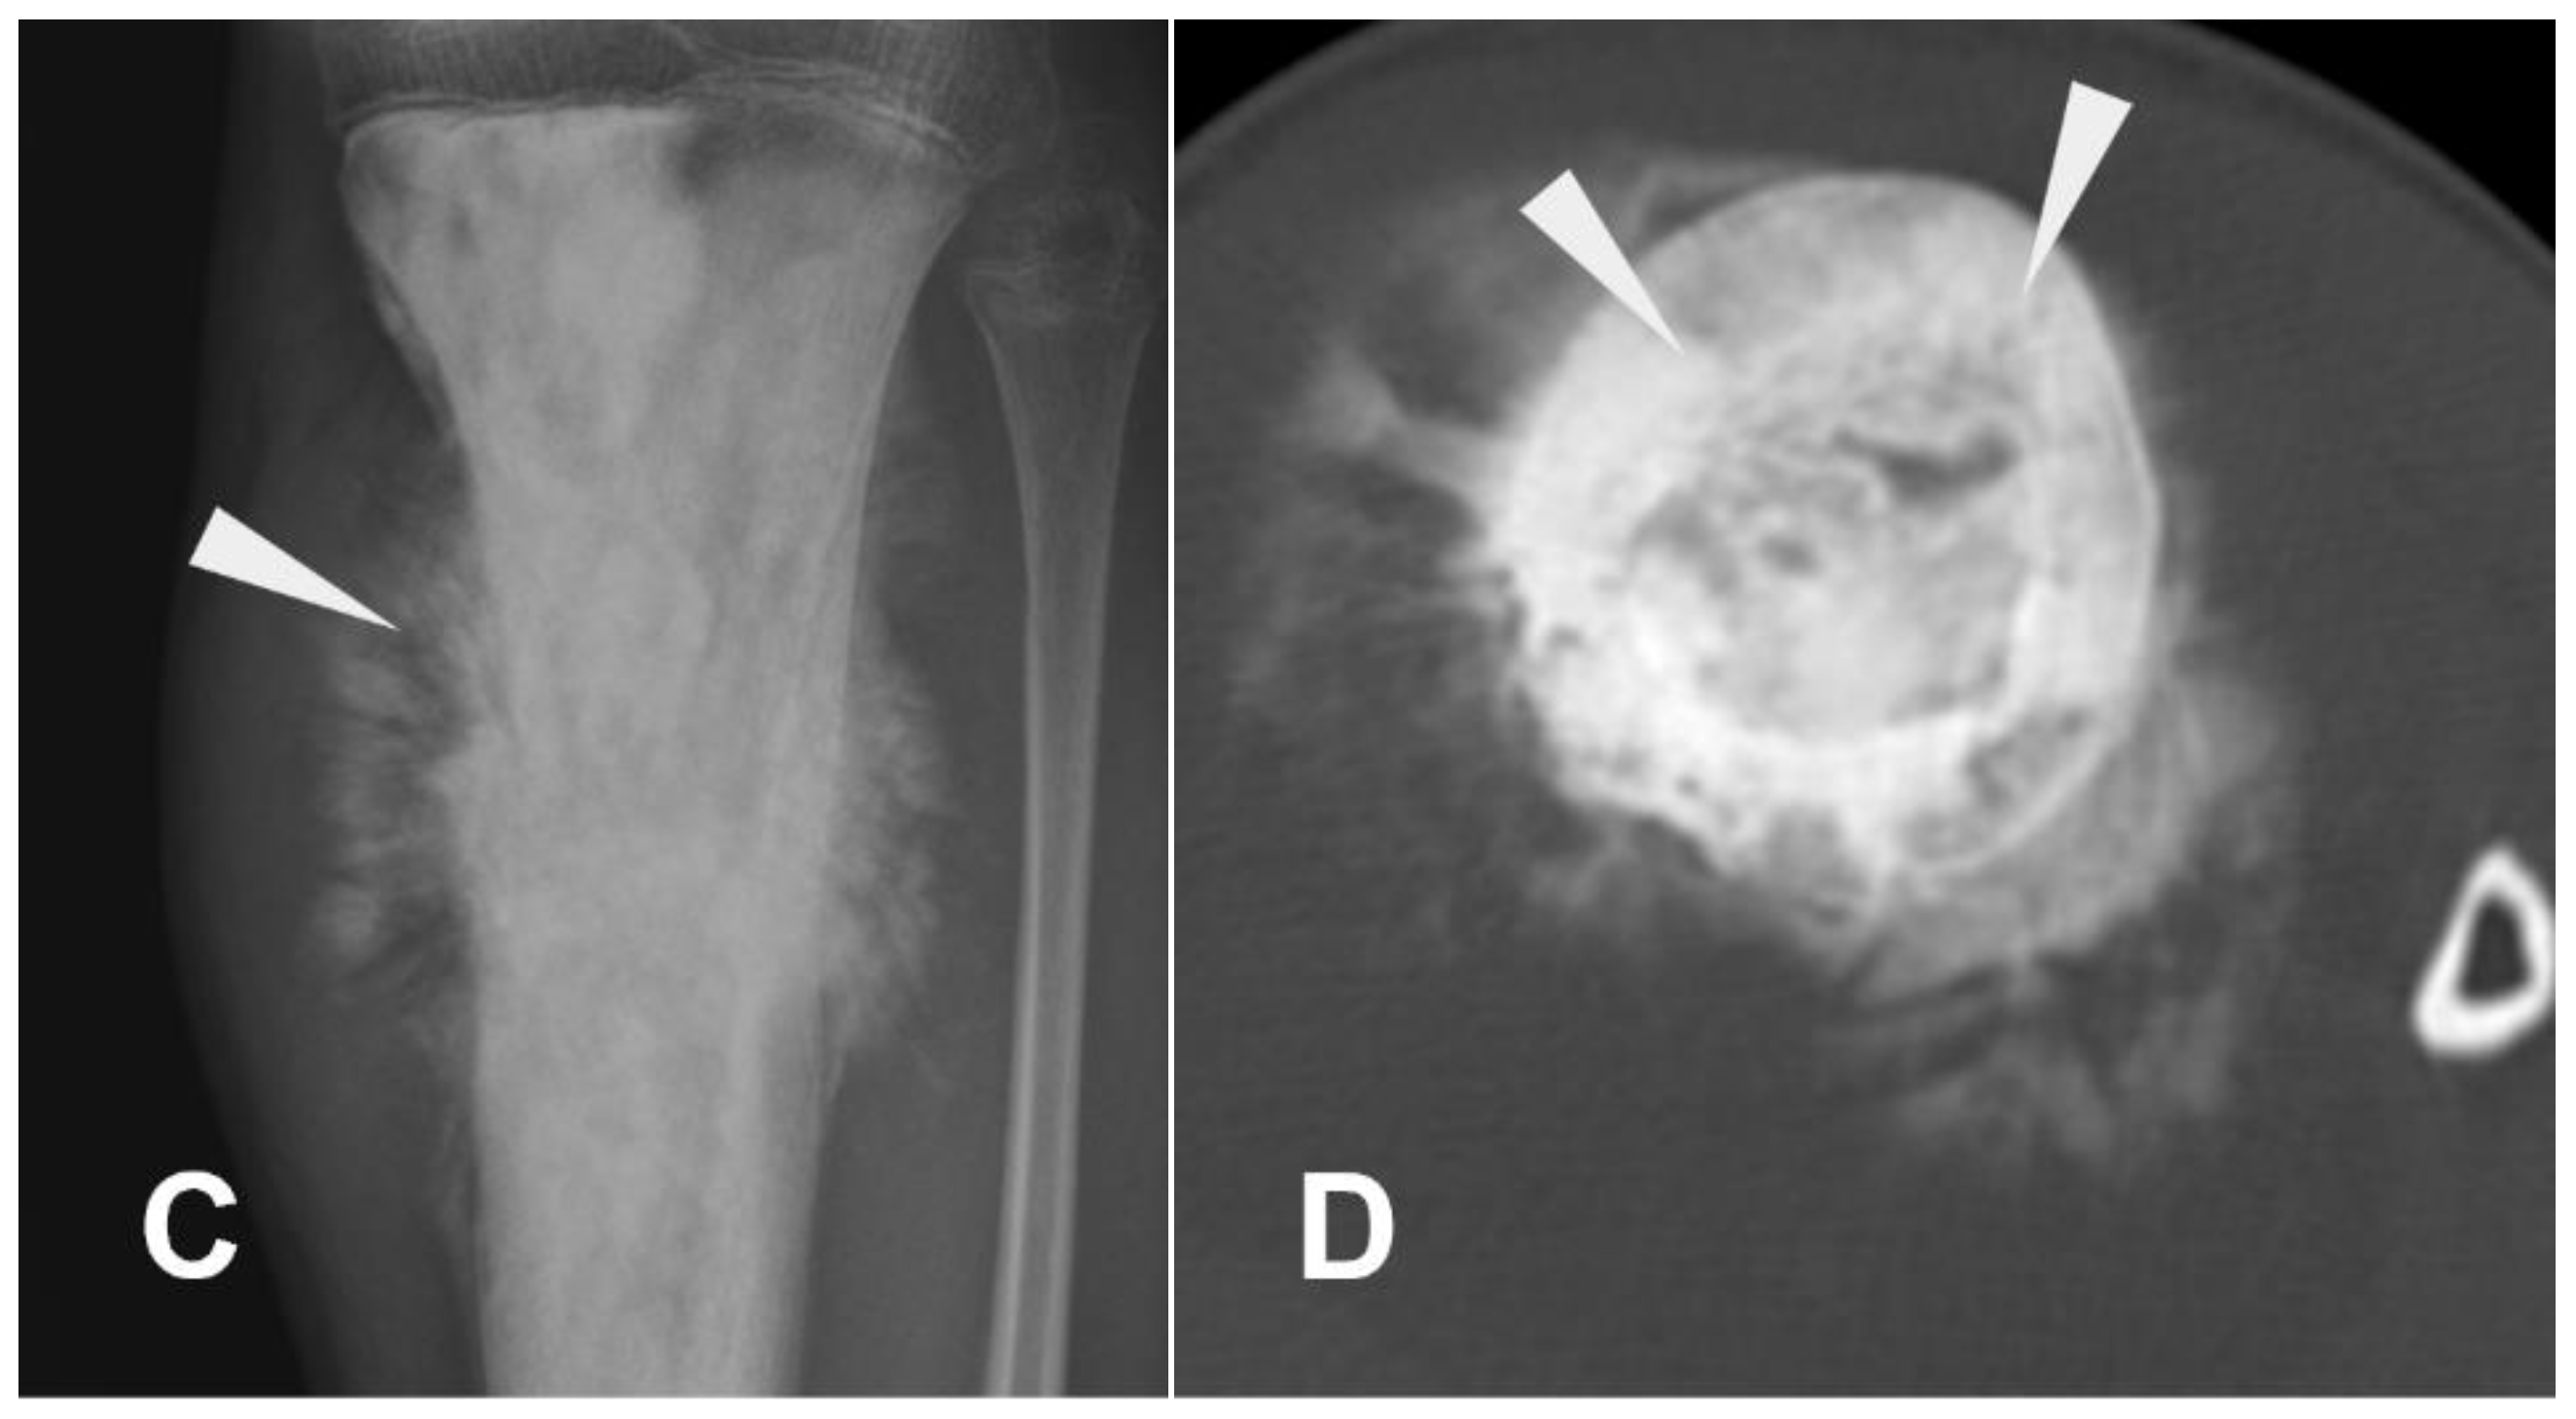

- Sangle, N.A.; Layfield, L.J. Telangiectatic Osteosarcoma. Arch. Pathol. Lab. Med. 2012, 136, 572–576. [Google Scholar] [CrossRef] [PubMed]

- Angelini, A.; Mavrogenis, A.F.; Trovarelli, G.; Ferrari, S.; Picci, P.; Ruggieri, P. Telangiectatic Osteosarcoma: A Review of 87 Cases. J. Cancer Res. Clin. Oncol. 2016, 142, 2197–2207. [Google Scholar] [CrossRef] [PubMed]

- Chan, C.W.; Kung, T.M.; Ma, L. Telangiectatic Osteosarcoma of the Mandible. Cancer 1986, 58, 2110–2115. [Google Scholar] [CrossRef] [PubMed]

- Shehadeh, A.M.; Haiba, M.A.; Henshaw, R.M.; Lack, E. Telangiectatic osteosarcoma of the patella. Orthopedics 2008, 8, 808. [Google Scholar] [PubMed]